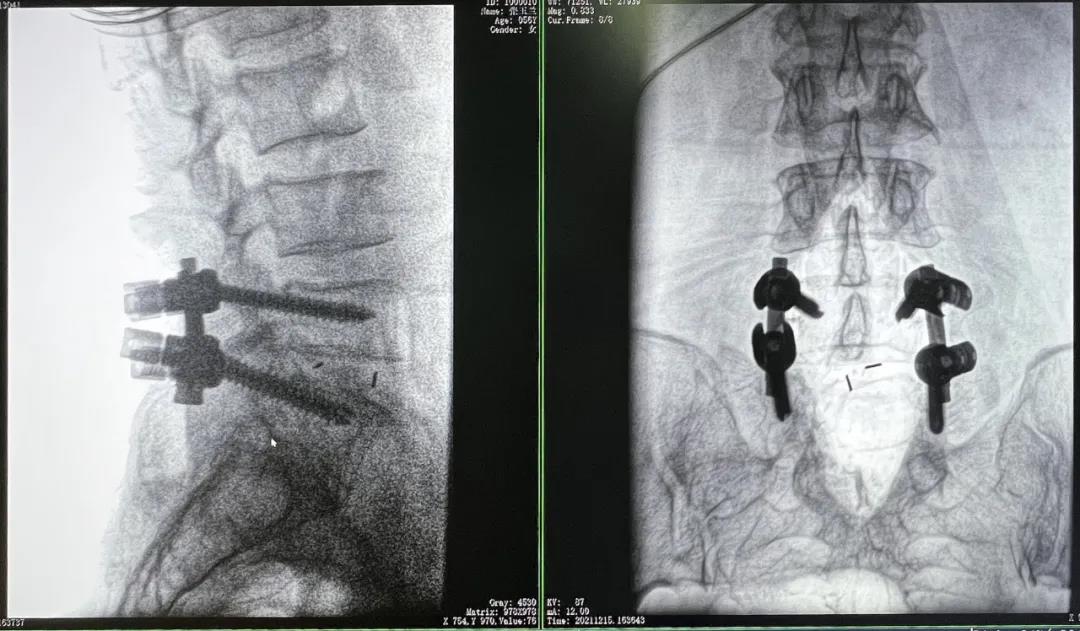

3D C形臂擺位及手術前二維影像

醫(yī)生在影像引導下在L5/S1椎弓根處打入醫(yī)用螺釘